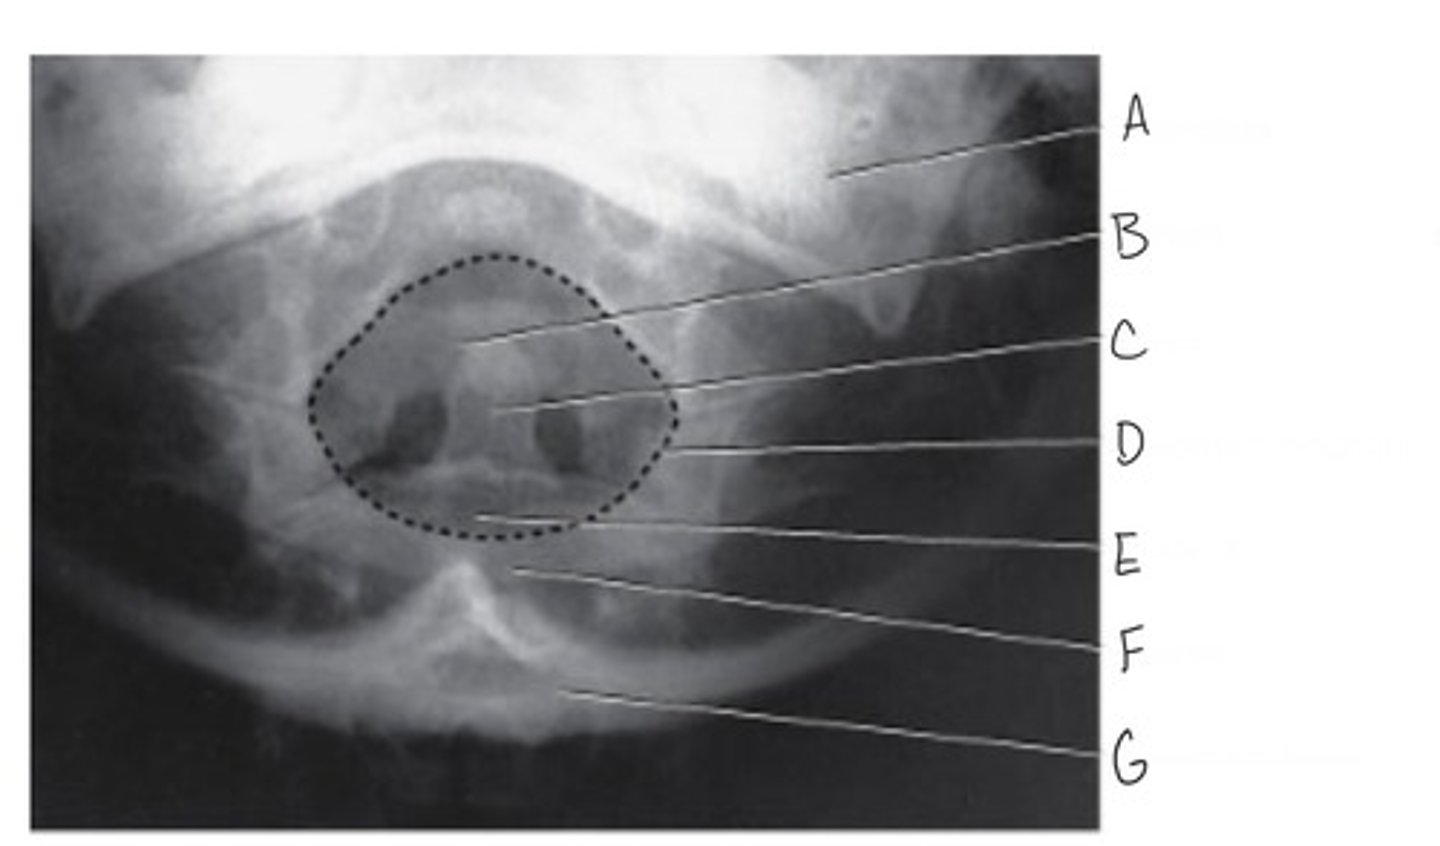

Mandibular rami

What is A?

Body of C3

What is B?

Inferior articular process

What is C?

Superior articular process

What is D?

Intervertebral disk

What is E?

Zygapophyseal joint

What is F?

Vertebra prominens (C7)

Why is G?